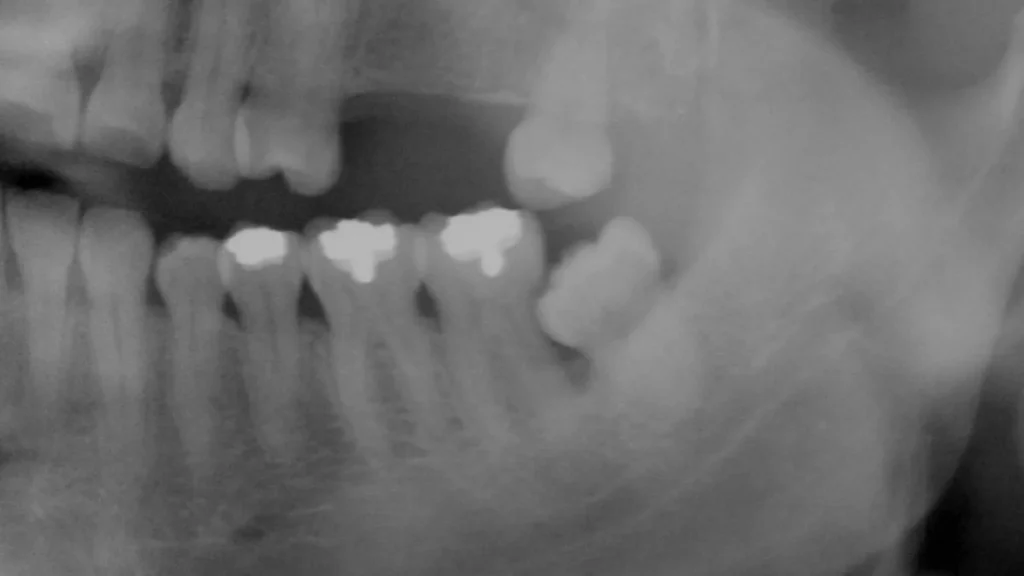

In this x-ray, we can see a partially impacted wisdom tooth that has led to periodontal disease, with heavy plaque accumulation causing significant bone loss around the tooth next to it. Bone loss, in turn, makes the otherwise healthy tooth more likely to require extraction in the future.